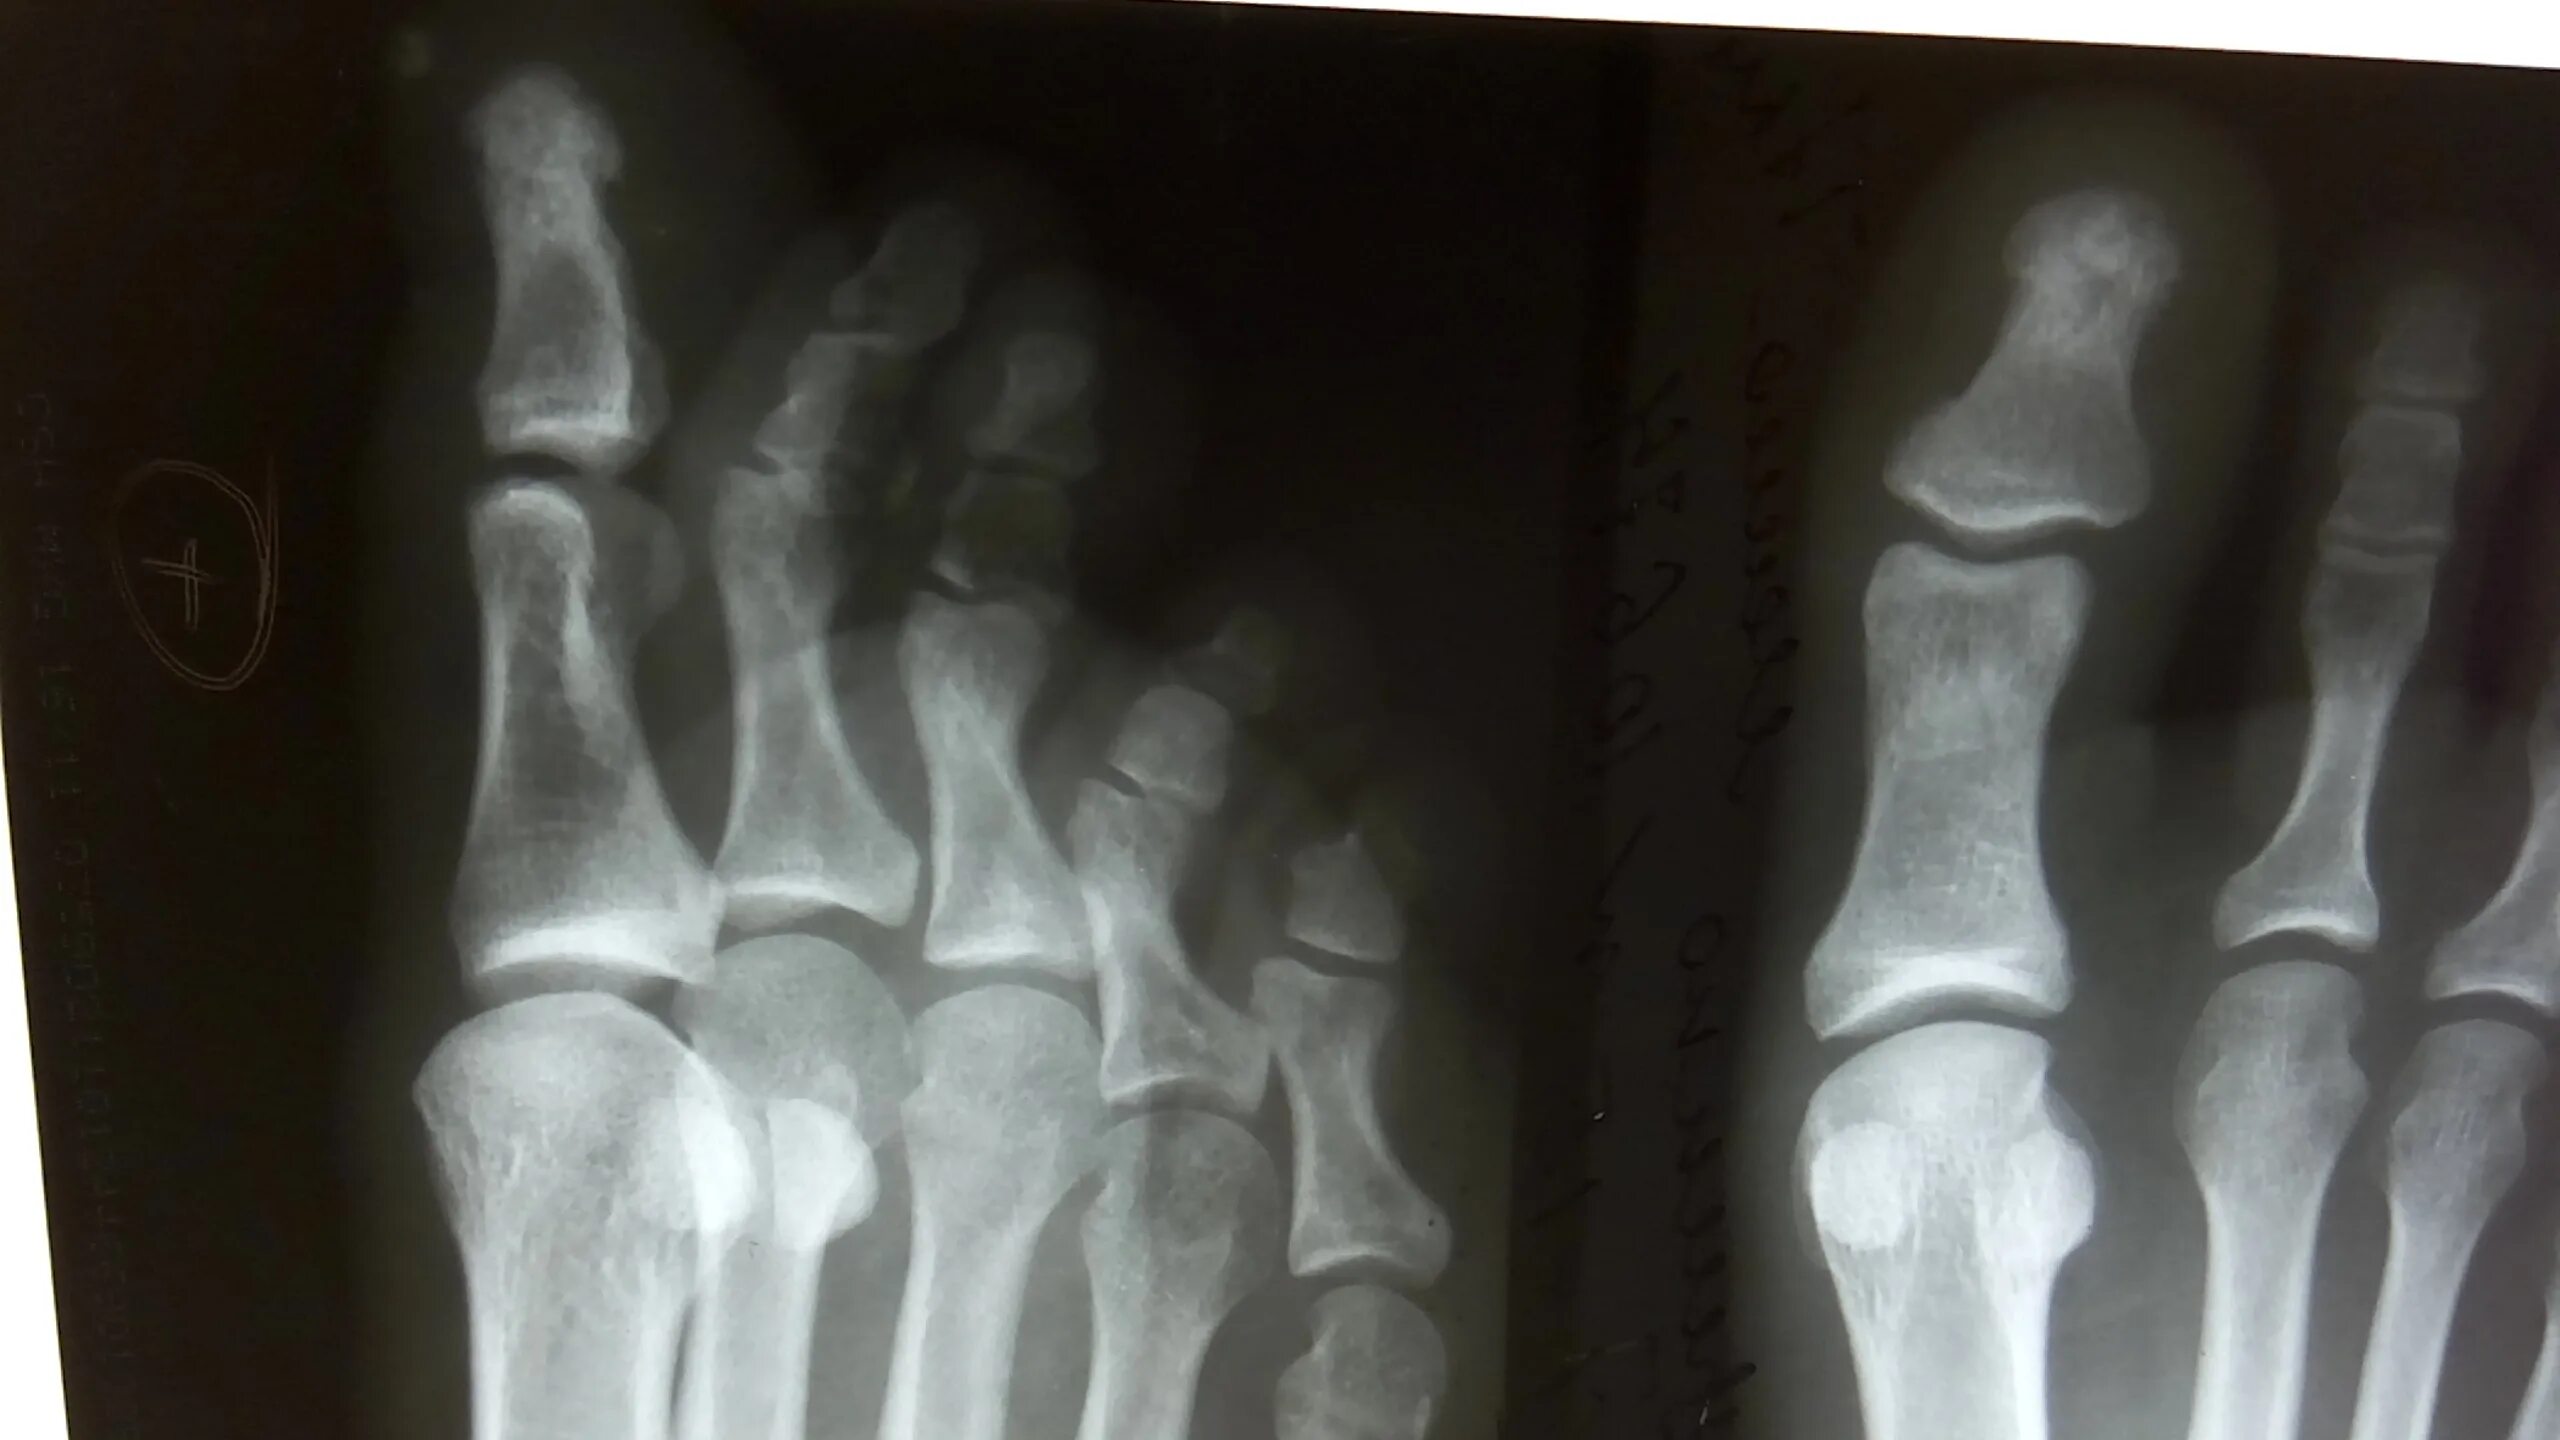

Закрытый перелом пальцев стопы мкб 10